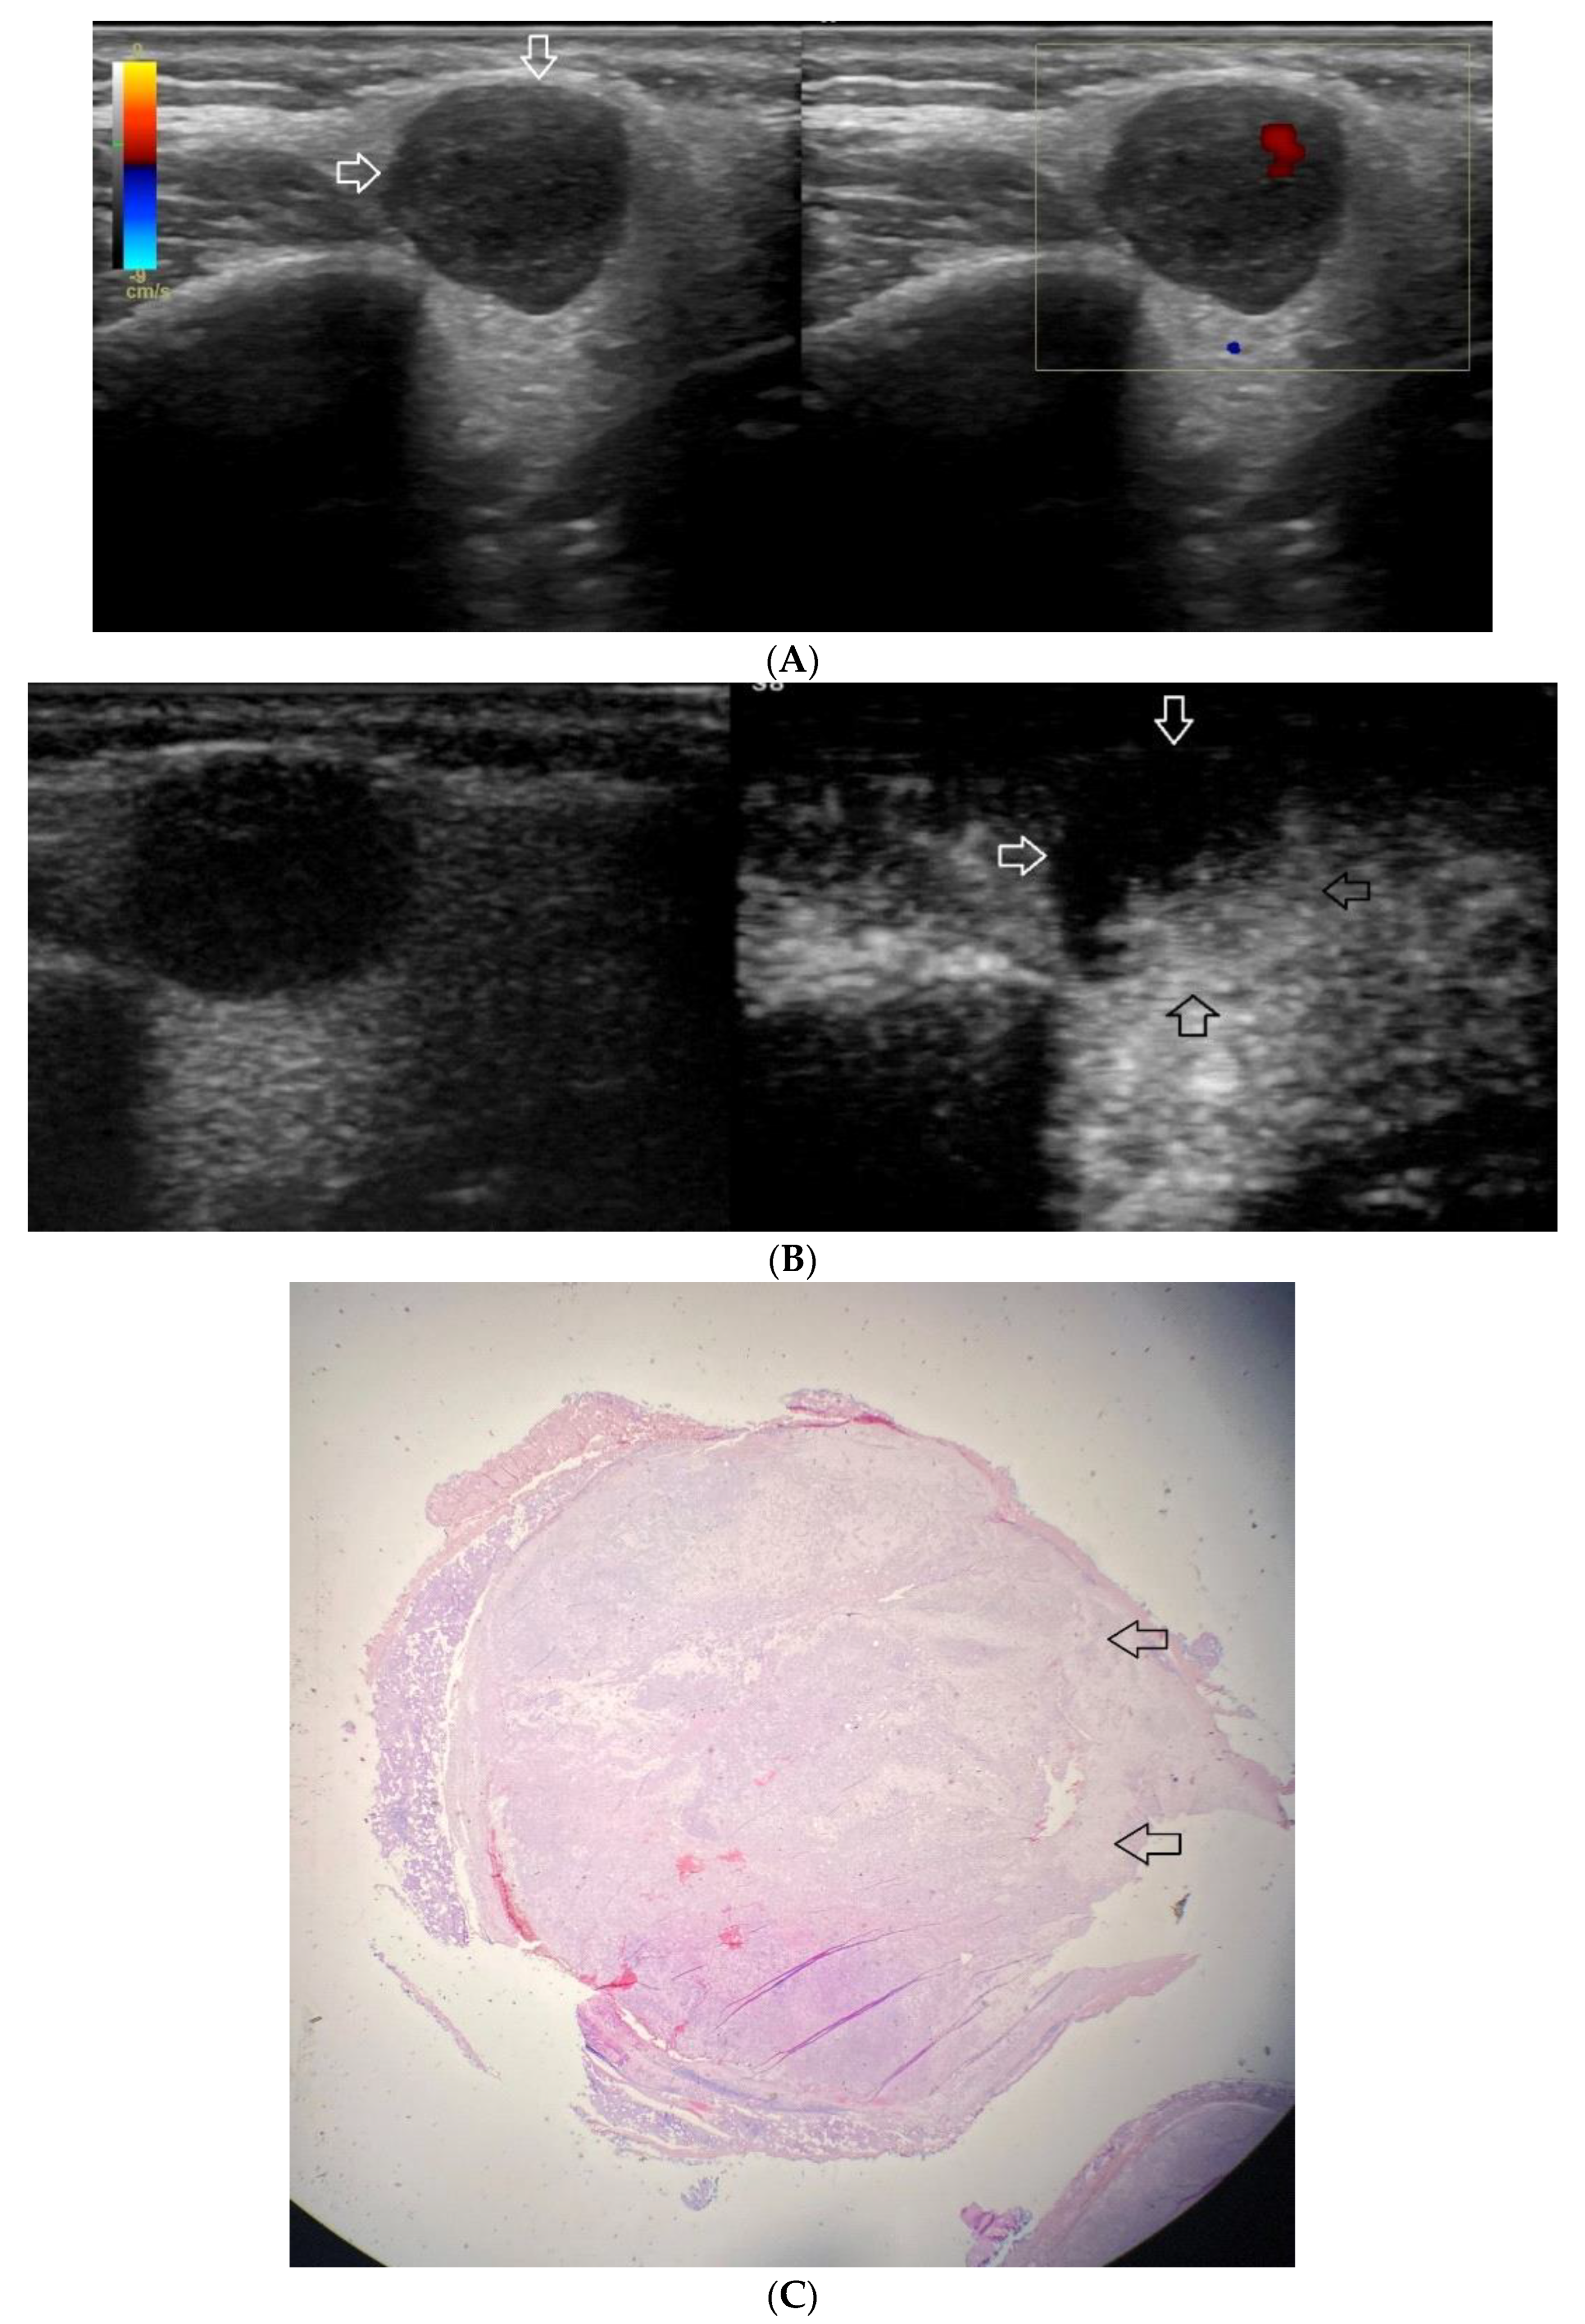

Figure 2.

(A−C) Pleomorphic adenoma. (A) Routine ultrasonographic examination in B presentation and colour Doppler: a well-demarcated focal lesion of a homogeneous echostructure (white arrows). On CD, low blood flow is observed. (B) Contrast-enhanced imaging in arterial phase: a strong homogeneous enhancement of a deeply located part of a lesion (black arrows). A superficial part is not enhanced (white arrows). (C) Pathomorphological image, H & E stain. A large area containing chondroid tissue (black arrows) with glandular tissue located beneath the lesion.